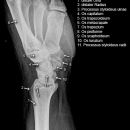

Handgelenk a.p.

Beurteilungskriterien

• Neigung der distalen Radiusgelenkfläche in der Frontalebene: 15 – 35°

• Längenverhältnis Radius – Ulna: Proc.styloideus radii überragt Gelenkfläche der Ulna um 9 –12mm (<9mm Ulna-Plusvariante, >12mm Ulnaminusvariante)

• Kontinuität der drei Karpalbögen:

Proximaler Bogen: proximale Gelenkflächenkonturen von Scaphoid, Lunatum und Triquetum

Mittlerer Bogen: distale Gelenkflächenkonturen von Sacphoid, Lunatum und Triquetum

Distaler Bogen: proximale Gelenkflächenkonturen von Capitatum und Hamatum

Fehlende Abgrenzbarkeit, Versatz oder Unterbrechung sind als pathologisch zu bewerten und deuten auf eine Luxation hin.

Trapezförmige Darstellung des Lunatum in Neutralstellung? Augenzeichen des Hamulus? Superposition von Pisiforme und Triquetum? Metacarpale III in Projektion innerhalb der Radiusgelenkfläche? Lunatum zu >50% über Radiusgelenkfläche? Cave: bei Radial- oder Ulnarduktion wandert das Lunatum in umgekehrter Richtung.

• M-förmiger Verlauf der Gelenkspalten der Carpometacarpalgelenke? Luxationsstellung in den Carpometacarpalgelenken (meist dorsale Luxation)?

• Gelenkspaltweiten des Radiocarpalgelenk 2 – 2,5mm, der Carpometacarpalgelenke 1 –2mm, distales Radioulnargelenk 2mm, Gelenksspaltweiten der Intercarpalgelenke 1,5 – 2mm

Cave: SL-Dissoziation (Ruptur des SL- Bandes, häufigste Gefügestörung): Terry-Thomas-Sign = SL-Spalt > 3mm, Siegelringzeichen = Ringförmige Transparenzminderung im mittleren Scaphoiddrittel durch orthograde Projektion der Taille infolge Rotation.

• Obliteration des Scaphoidfettstreifens?

• Täuschungsmöglichkeiten durch Vielzahl akzessorischer Ossikel (abgerundete, zirkulkär-geschlossene Kortikalis), geteilte Handwurzelknochen (Scaphoid, Lunatum, Pisiforme) und Gefäßkanälchen

• Target areas leicht zu übersehender Frakturen: distales Radioulnargelenk, Processus styloideus radii et ulnae, Basen der Metacarpalia (v.a. MCP I), Hamulus.

• Grundsätzlich gilt: unklare Verhältnisse ->CT-Indikation